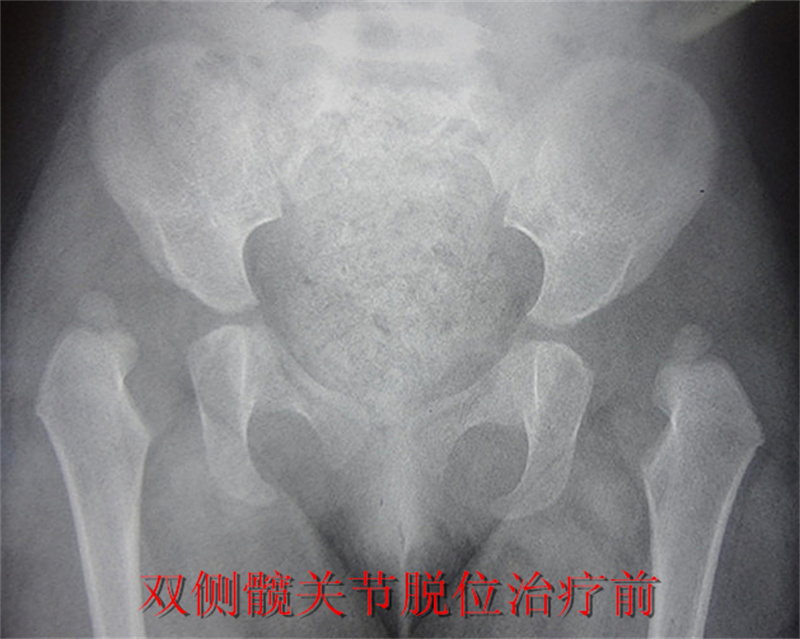

徐州市儿童医院科普:发育性髋关节脱位的早期诊断与治疗